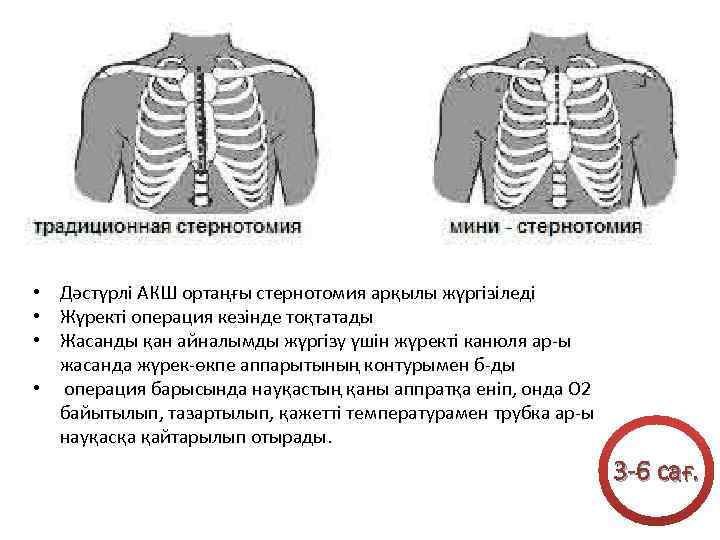

• Дәстүрлі АКШ ортаңғы стернотомия арқылы жүргізіледі • Жүректі операция кезінде тоқтатады • Жасанды қан айналымды жүргізу үшін жүректі канюля ар-ы жасанда жүрек-өкпе аппарытының контурымен б-ды • операция барысында науқастың қаны аппратқа еніп, онда О 2 байытылып, тазартылып, қажетті температурамен трубка ар-ы науқасқа қайтарылып отырады. 3 -6 сағ.

• Дәстүрлі АКШ ортаңғы стернотомия арқылы жүргізіледі • Жүректі операция кезінде тоқтатады • Жасанды қан айналымды жүргізу үшін жүректі канюля ар-ы жасанда жүрек-өкпе аппарытының контурымен б-ды • операция барысында науқастың қаны аппратқа еніп, онда О 2 байытылып, тазартылып, қажетті температурамен трубка ар-ы науқасқа қайтарылып отырады. 3 -6 сағ.